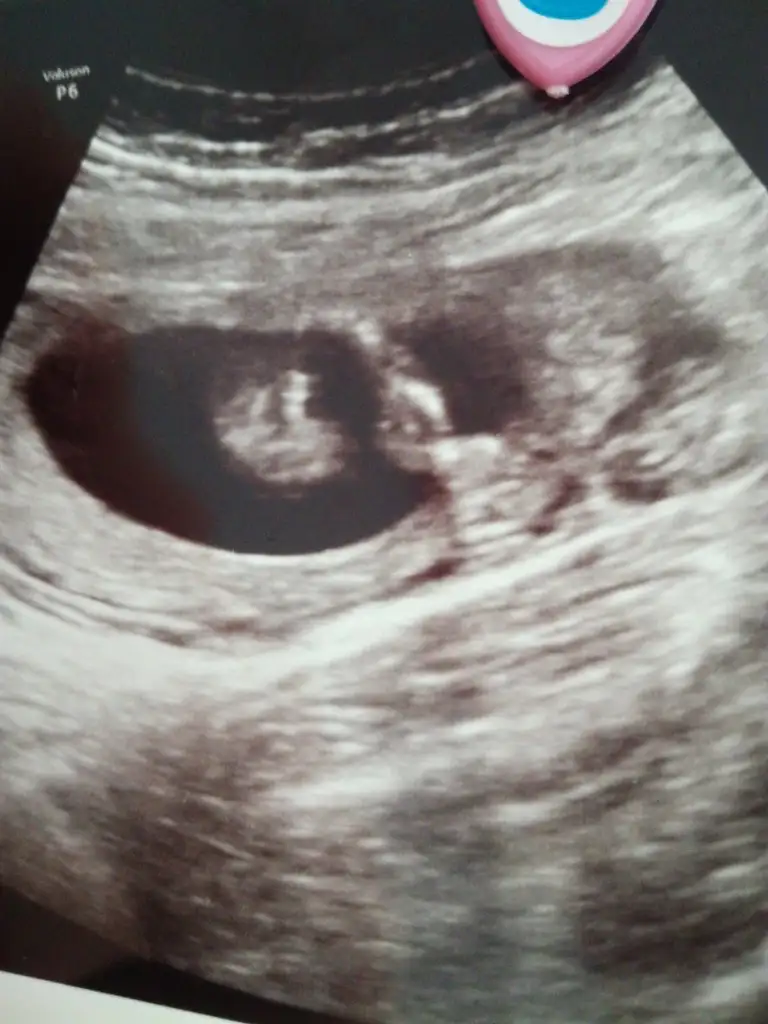

Doktordan geldik şimdi canım baya zor gördü birini muhtemelen oda senin emin olamadıgındı çok inceledi iki hafta sonra değişmezse ikisini de kız gördüCumlemizinkini sağlıkla nasip etsin rabbim

Sağlıkla gelsinler canım evet biri net değildiDoktordan geldik şimdi canım baya zor gördü birini muhtemelen oda senin emin olamadıgındı çok inceledi iki hafta sonra değişmezse ikisini de kız gördü

Evet ikisi kız gibi sankiAmin ininşaallahvalla hiç poz vermediler hep kapattılar ama doktor ikisinde de çengel falan dedi sanırım cinsiyet kısımları bunlar ben hiç bişey anlamıyorum ama attım bugün tam 14hafta bitti

Evet ikisi kız gibi sanki